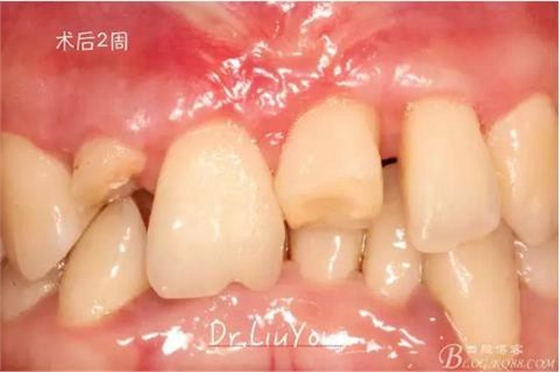

骨塊固定兩周后復查,如上圖

在松動牙固定的同時,嘗試保留B1唇側折裂牙槽骨塊,拆除縫線后,局部沖洗,牙周塞治劑覆蓋并固定游離骨塊。囑患者加強口腔衛(wèi)生,氯己定漱口液含漱,兩周后復查。兩周后拆除塞治劑,骨塊仍為游離活動狀態(tài),去除游離骨塊,局部沖洗上藥。